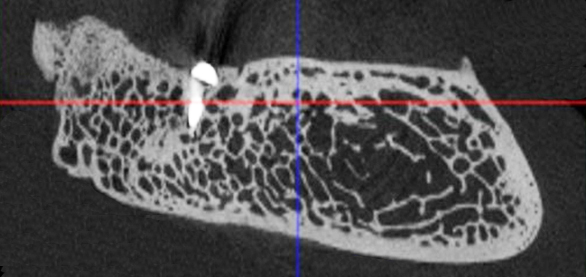

Рис. 2. Поперечный срез альвеолярной кости верхней челюсти человека в проекции отсутствующего премоляра (А) и альвеолярная кость нижней челюсти человека в проекции отсутствующего моляра (Б). 3D-КЛКТ

Учитывая выше перечисленные недостатки, поиск новых областей и способов хирургического доступа для создания экспериментальной модели исследования остеопластических материалов является актуальным. Нас заинтересовало использование в качестве экспериментальной живой модели область локтевого отростка передних конечностей овцы. В доступной литературе нами не встречено упоминаний об использовании локтевых отростков овец с целью формирования костных дефектов для оценки регенераторного потенциала остеопластических материалов. Вероятно, это обусловлено боязнью риска травматизма локтевого отростка в ходе формировании дефекта при использовании классического хирургического инструментария – сверл и фрез большого диаметра. Между тем очевиден ряд преимуществ данной области – схожее анатомическое строение и архитектоника с альвеолярной частью челюстей человека. Локтевой отросток имеет наружный кортикальный слой и внутренний, представленный губчатым веществом с костномозговыми пространствами небольшого размера (рис. 1, 2).